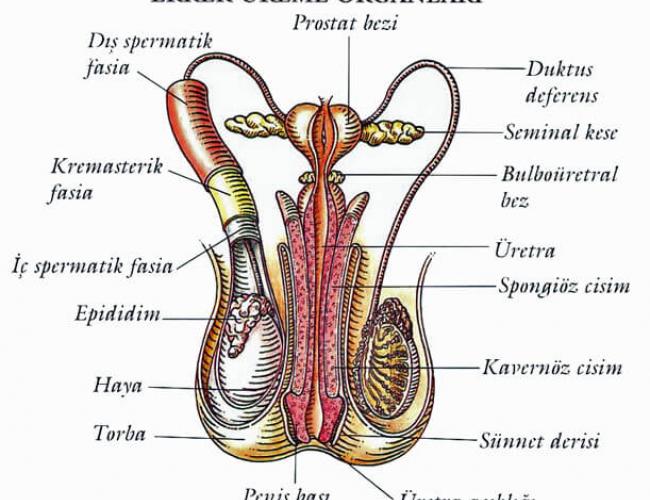

Çocuk sahibi olmak isteyen çiftlerin ortalama %15-20 ‘ sinde kısırlık – infertilite sorunu ile karşılaşmaktayız. Bunlarında % 40-50 sinde erkeğe bağlı sorunlardan dolayı...

Doğuştan sperm kanalının oluşmaması ( sperm kanalı – vaz deferensin olmaması ): Erkeklerde sperm taşıyıcı sisteminin ( vaz deferens ) iki yada tek taraflı olarak...